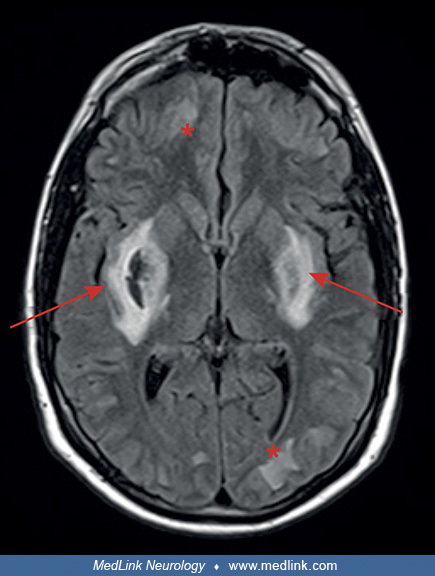

CADASIL/CARASIL

cerebral autosomal dominant/recessive arteriopathy with subcortical infarcts and leukoencephalopathy

NOTCH3 mutations

causes progressive cognitive decline, recurrent ischemic strokes (often lacunar), migraines

MRI features symmetric WM hyperintensities, including in anterior temporal poles